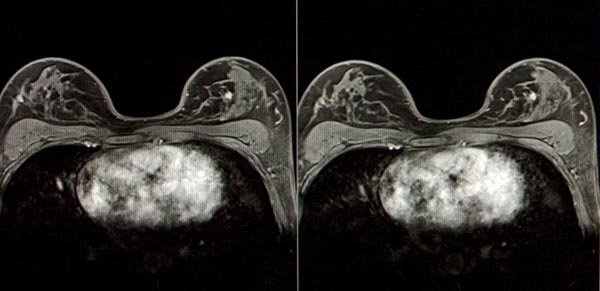

Нормальная структура ткани характеризуется неровным контуром и тонкими пальцевидными выпячиваниями в окружающую жировую клетчатку. При раке молочной железы КТ-сканирование чаще всего выявляет солидное образование неправильной формы. Диагностируют степень прорастания фасциальных листков и инфильтрации в грудную стенку на стороне поражения. Исследование рецидива рака значительно усложняют наличие фиброзных изменений после лучевой терапии, послеоперационные рубцы, а также отсутствие окружающей жировой клетчатки. Поэтому особое внимание уделяется регионарным лимфоузлам и костям, чтобы не пропустить метастазы в позвоночник.